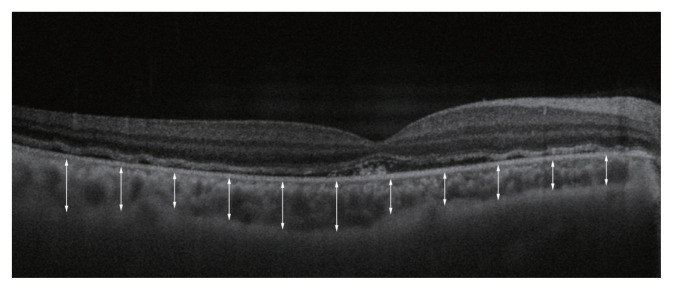

Methods: A retrospective observational study was conducted on patients who underwent surgery for recurrent RRD from November 2019 to March 2023. Choroidal thickness was measured using optical coherence tomography at baseline and at 2 and 6 months postoperatively. The study analyzed the impact of various factors on choroidal thickness changes.

Results: The study included 33 patients, demonstrating a significant decrease in choroidal thickness in the surgical eye compared to the fellow eye over a 6-month period. In the univariate analysis, changes in choroidal thickness were significantly correlated with changes in central retinal thickness (p = 0.048) from baseline to 2 months and with proliferative vitreoretinopathy (PVR) grade from 2 to 6 months (p = 0.009) and from baseline to 6 months (p = 0.020). In the multivariate analysis, an association was found between changes in choroidal thickness from 2 to 6 months and PVR grade (p = 0.030).

Conclusions: The findings indicate that surgical reattachment in eyes with recurrent RRD leads to a significant reduction in choroidal thickness. The extent of this reduction is influenced by the severity of PVR, highlighting the importance of considering PVR severity when evaluating surgical outcomes in patients with recurrent RRD.